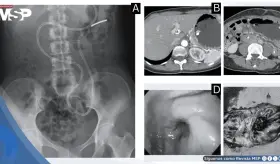

La paciente presentó cambios en el hábito intestinal y sangrado rectal con imágenes compatibles con lesiones estenosantes, inicialmente sospechosas de neoplasia sincrónica.

El estudio histológico confirmó un adenocarcinoma mucinoso de células en anillo de sello de vejiga con invasión muscular y diseminación metastásica pulmonar y ósea.